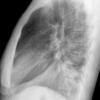

Case 2  Lingular pneum Lat

Date: 04/17/2005

Views: 7024